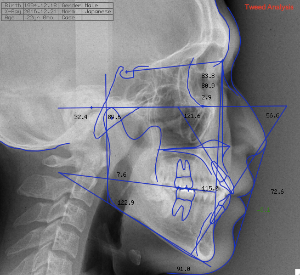

ステップ3. レントゲン (パノラマ,セファロ)撮影 口腔内写真撮影

横顔のレントゲン及び実際の横顔のデジタル画像のコンピューターへの入力の後、

あなたの骨格、歯の状態に合わせて、治療を受けた場合の横顔の変化のシュミレーションを行います。

ステップ3. レントゲン(パノラマ、セファロ)撮影・口腔内写真撮影